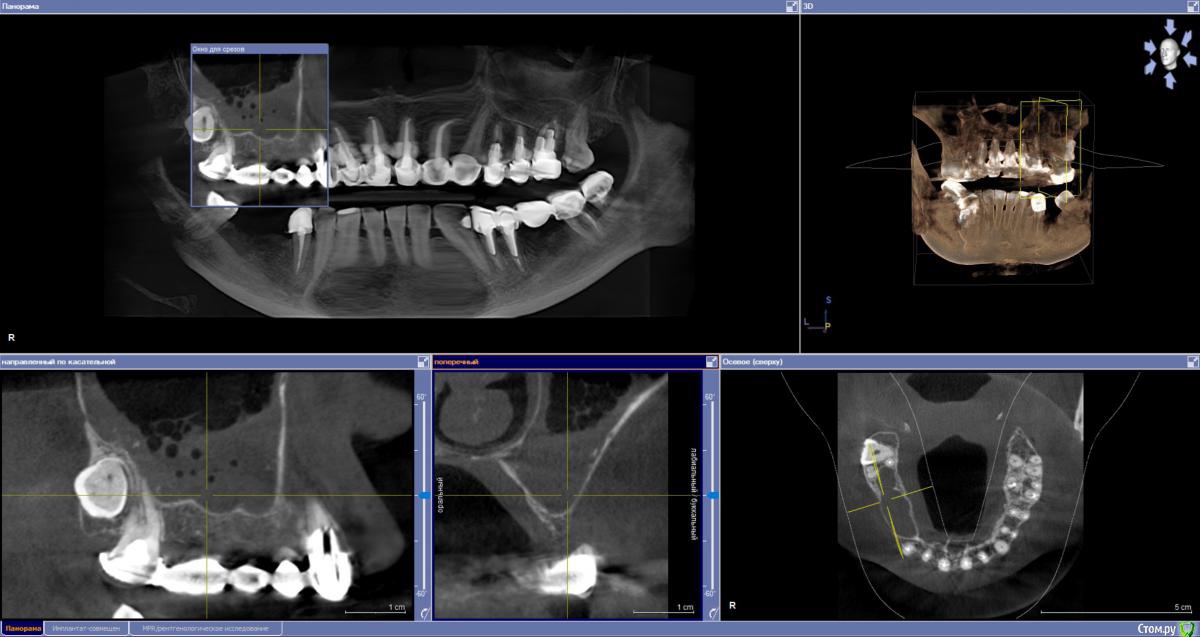

sabik Опубликовано 13 марта, 2019 Поделиться Опубликовано 13 марта, 2019 Хотела б услышать мнение по поводу возможности установки имплантов, ходила в несколько клиник, все говорят разное, общее только то, что на КТ видно, что нет кости вообще, проблема с верхней пазухой,нужна операция лор, еще вопрос можно ли повторить этот мост наверху при отсутствии трех зубов? Не хотят браться за меня нигде Еще беспокоит тупая ноющая боль время от времени, на снимке слева внизу, причину не находят. Подскажите, есть ли зубы на удаление, и какие проблемы видно в общем? Ссылка на комментарий

sabik Опубликовано 14 марта, 2019 Автор Поделиться Опубликовано 14 марта, 2019 Болтается мост сверху, на снимке слева, и беспокоит тупая боль снизу на этой же стороне, жую почти 2 года другой стороной, нужно менять коронки и где возможно установить импланты. Хочу услышать мнение профессионалов по снимку, что можно сделать в моей ситуации. По КТ кости не хватает нигде. Ссылка на комментарий

sabik Опубликовано 23 марта, 2019 Автор Поделиться Опубликовано 23 марта, 2019 Выкладывайте срезы КТПо инструкции с сайта не смогу выложить срезы, нет соответствующей папки (Dicom), но сделала скриншоты (прикреплены к сообщению) проблемных мест в программе. Если не совсем то, скажите, как лучше сделать скриншоты (или видео). Очень нужно мнение специалистов! Ссылка на комментарий

kramer Опубликовано 23 марта, 2019 Поделиться Опубликовано 23 марта, 2019 Источник боли с правой стороны на нижней челюсти пока неясен. Что касается верх право, чтобы ставить имплантаты, надо предварительно делать синус-лифт, до синус-лифта надо приводить пазуху в порядок с помощью ЛОР врача Ссылка на комментарий

sabik Опубликовано 23 марта, 2019 Автор Поделиться Опубликовано 23 марта, 2019 Источник боли с правой стороны на нижней челюсти пока неясен. Что касается верх право, чтобы ставить имплантаты, надо предварительно делать синус-лифт, до синус-лифта надо приводить пазуху в порядок с помощью ЛОР врача Спасибо, что ответили! Возможно ли поставить импланты снизу справа? А слева какая ситуация, есть ли кисты. удалять надо зубы или нет, все говорят разное просто, очень сложно понять кто прав(( Ссылка на комментарий

Nazim_NV86 Опубликовано 23 марта, 2019 Поделиться Опубликовано 23 марта, 2019 Возможно ли поставить импланты снизу справа? Возможно. А слева какая ситуация, есть ли кисты. удалять надо зубы или нетПроблемы есть. Нужно во рту смотреть и томограмму. Вы срезы не те выкладываете. Этот Galileos только с диска читается. Ссылка на комментарий

sabik Опубликовано 2 апреля, 2019 Автор Поделиться Опубликовано 2 апреля, 2019 Предлагают два варианта постановки имплантов справа внизу: первый вариант - поставить 2 импланта вместо 5 и 6 зуба, с подсадкой кости, расщеплением гребня, а второй вариант- 2 импланта вместо 5 и 7 зуба, с подсадкой кости только на 5 зубе, а на место 7-го имплант сразу ровно поставленный, и позже мост . 7 зуб живой, но с наклонном, боль есть тупая, говорят может он один там и нагрузка идет на него, не знаю, из-за этого может болеть он временами или нет, перидонтальная щель расширена чуть тоже. Как считаете, какой вариант имплантации лучше? Ссылка на комментарий